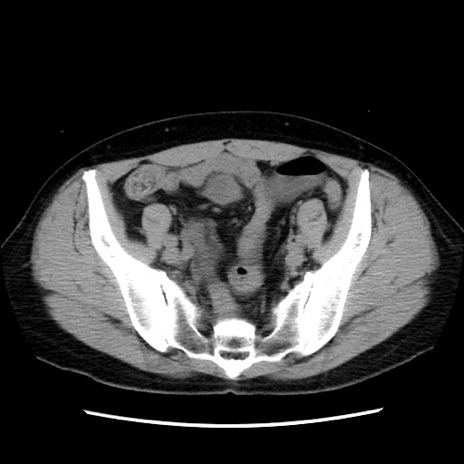

冠状断像

【症例】 50歳代女性

【主訴】 腹痛

【現病歴】前日生レバーを食べた。今朝に排便あり。 昼前に突然発症の腹痛を生じ、当院救急外来を受診した。

【身体所見】 意識清明、腹部:平坦、軟、下腹部やや左を中心に圧痛・反跳痛あり、筋性防御あり